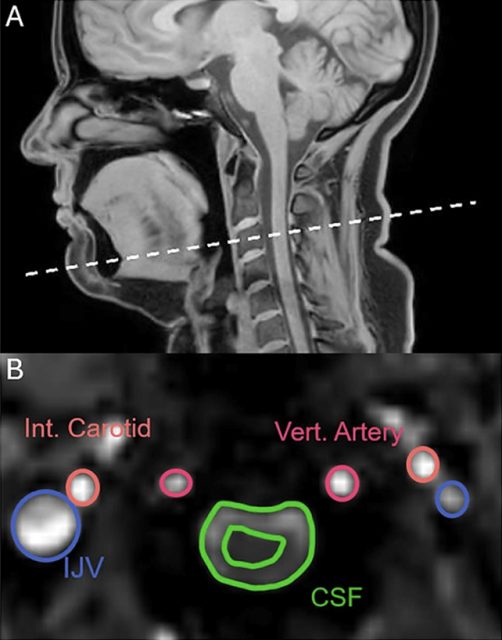

Οι επιστήμονες χρησιμοποίησαν μαγνητική τομογραφία σε 22 υγιείς εθελοντές. Κατά τη διάρκεια των σαρώσεων οι συμμετέχοντες κλήθηκαν να χασμουρηθούν, να πάρουν βαθιές αναπνοές, να καταστείλουν το χασμουρητό και να αναπνεύσουν φυσιολογικά.

Επειδή το χασμουρητό και η βαθιά αναπνοή μοιάζουν μηχανικά, οι ερευνητές περίμεναν παρόμοια αποτελέσματα. Αντί γι’ αυτό εντόπισαν μια βασική διαφορά. Στο χασμουρητό, το εγκεφαλονωτιαίο υγρό μετακινείται σε αντίθετη κατεύθυνση σε σχέση με τη βαθιά αναπνοή.

Η ανάλυση έδειξε επίσης ότι τόσο το χασμουρητό όσο και οι βαθιές αναπνοές αυξάνουν τη φλεβική απορροή αίματος από τον εγκέφαλο. Αυτό δημιουργεί περισσότερο διαθέσιμο χώρο ώστε να εισρεύσει φρέσκο αίμα.

Στα αρχικά στάδια του χασμουρητού καταγράφηκε και σημαντική αύξηση της ροής από την καρωτιδική αρτηρία προς τον εγκέφαλο, περίπου κατά ένα τρίτο. Αντίθετα, η κατεύθυνση της ροής του αίματος δεν αντιστρέφεται όπως συμβαίνει με το εγκεφαλονωτιαίο υγρό.